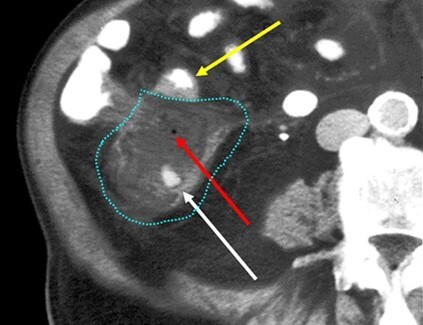

Appendicolith (white arrow) with a large abscess (dashed blue line) containing a foci of air (red arrow)